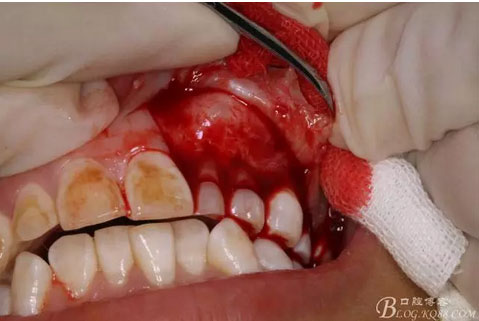

圖9.從兩個切口的連接處開始翻瓣。全厚瓣。

圖10.暴露出骨性隆起。骨質表面光滑。

圖11.暴露出23的牙尖,牙尖垂直于唇側粘膜。建議拔除,患者同意。

圖12.用小骨鑿去除覆蓋在牙瘤表面的骨質。發(fā)現牙瘤的包膜。